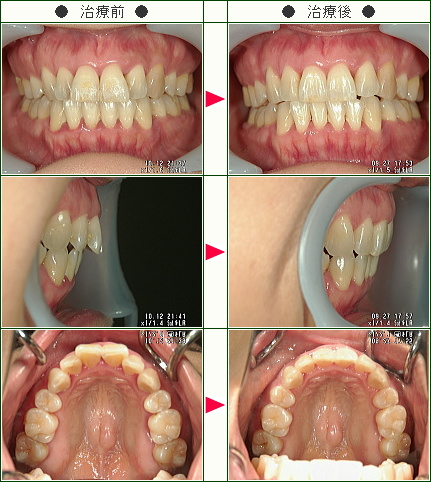

☆出っ歯矯正症例(C・I様 51歳 女性)

▼患者様の感想

たまたまネットで歯科医院の検索をしていたら「部分矯正」という言葉を見つけ興味を持ち南青山デンタルクリニックのHPを見ました。

良心的な雰囲気と料金も安く治療できるということで治療することを決めました。

料金も最初にお支払いするだけでよかったので、わかりやすく安心して治療を受ける事ができて良かったと思います。